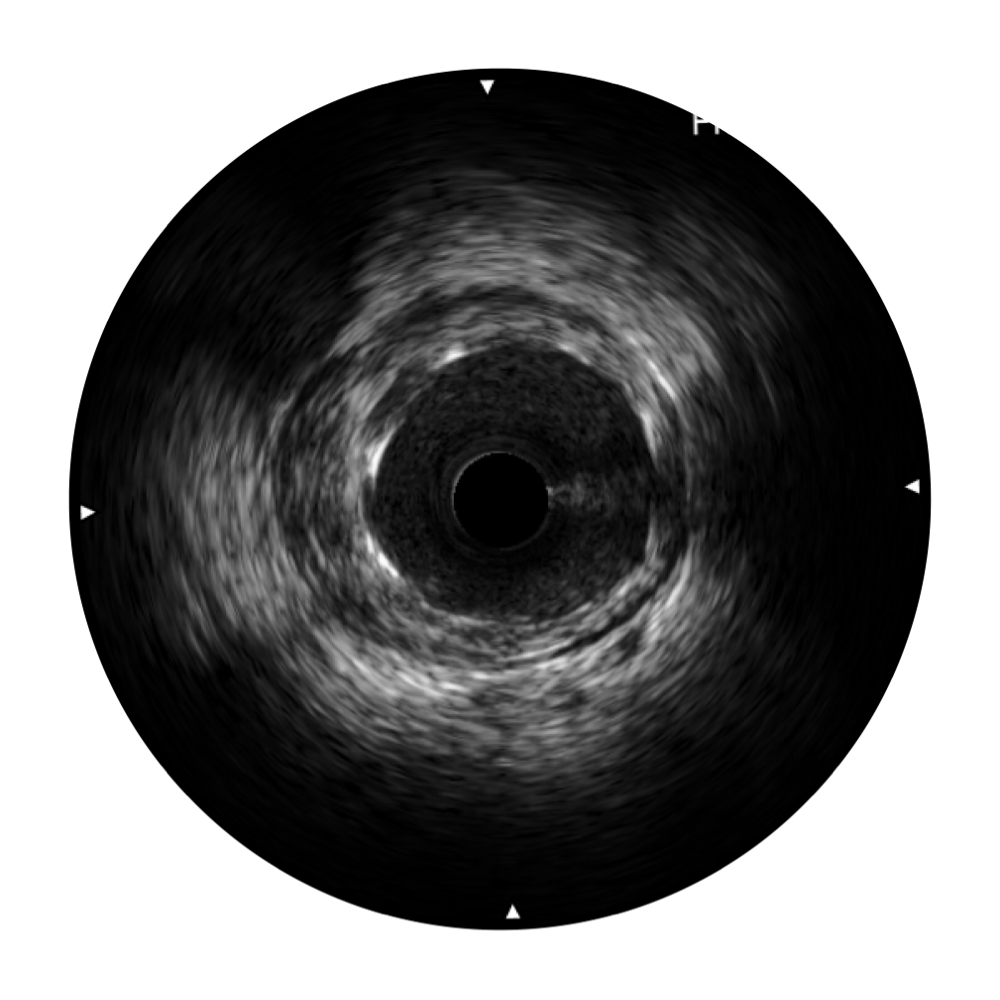

血管内超声(IVUS) 通过对病变程度、性质和累及范围的精确判断,可帮助选择治疗策略和方法,指导介入治疗过程,能够降低主要不良心血管事件,改善预后,在复杂病变介入治疗中用于指导支架置入的优势更为明显。血管内超声(IVUS)已成为精准心血管介入治疗的“金标准”。

银河优越会始终关注未满足的临床需求:超宽频成像技术同时提供高清分辨力和充足穿透深度,适应不同血管结构的治疗引导;智慧赋能,简化操作,降低临床应用难度和缩短学习曲线。